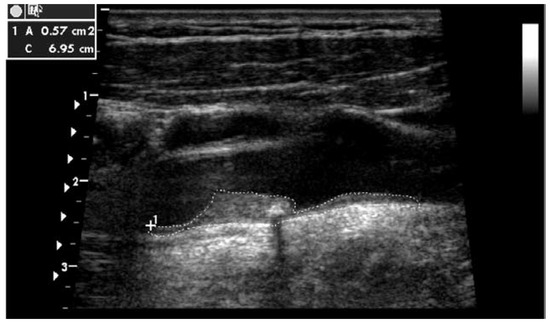

Purpose: To compare the effectiveness of assessment tools for 10-year cardiovascular risk in physician-referred Swiss patients. Material and Methods: The risk evaluation according to the Prospective Cardiovascular Münster algorithm, adapted for the Swiss population (CH-PROCAM) was defined as PROCAM corrected by [...] Read more.

Purpose: To compare the effectiveness of assessment tools for 10-year cardiovascular risk in physician-referred Swiss patients. Material and Methods: The risk evaluation according to the Prospective Cardiovascular Münster algorithm, adapted for the Swiss population (CH-PROCAM) was defined as PROCAM corrected by the factor 0.7 for Switzerland in all subjects ≥50 years of age and 0.18 in women <50 years in age. In these subjects, CH-PROCAM, the algorithm of the European Atherosclerosis Society (EU-SCORE), coronary calcium score percentiles (CS%), and total plaque area of the carotid arteries (TPA) were available. Posttest probabilities (PTP) for CS% and for TPA were calculated by using the Bayes formula. Agreement for starting an LDL cholesterol (LDLC)-lowering therapy between CH-PROCAM and CH-PROCAM-PTP was assessed in intermediate risk patients. Results: CH-PROCAM identified 17 (10%) and EU-SCORE 42 (24%) out of 175 individuals at high risk (p = 0.0006, weighted kappa (wK) = 0.45). CH-PROCAM-PTP identified 30 (17%) and EU-SCORE-PTP 66 (38%) individuals at high risk (p <0.001, wK = 0.26). The 19 patients with vascular disease (9% of 213) were detected by CH-PROCAM-PTP (receiver operating characteristics (ROC) 0.69, p = 0.002), but not by the other methods. Agreement to start a LDLC-lowering therapy in intermediate risk subjects was moderate (wK = 0.54). Conclusion: CH-PROCAM classified patients at high risk significantly less often than EUSCORE. EU-SCORE-PTP appears to substantially overestimate the true risk. What is most important, CH-PROCAM-PTP identified patients with clinical vascular disease, as shown by ROC analysis. Therefore, CH-PROCAMPTP currently represents a valuable method for further stratifying risk in primary care patients who have been defined by CH-PROCAM as being at intermediate risk, and may be helpful to correctly identify subjects who deserve an LDL lowering therapy. Full article

Figure 1